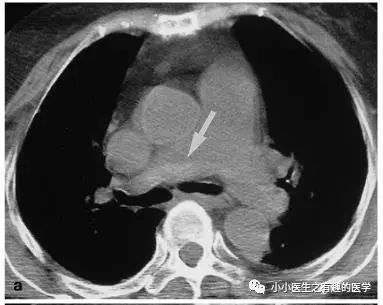

如图,高密度影的那一条。

不怕,有增强CT证实。